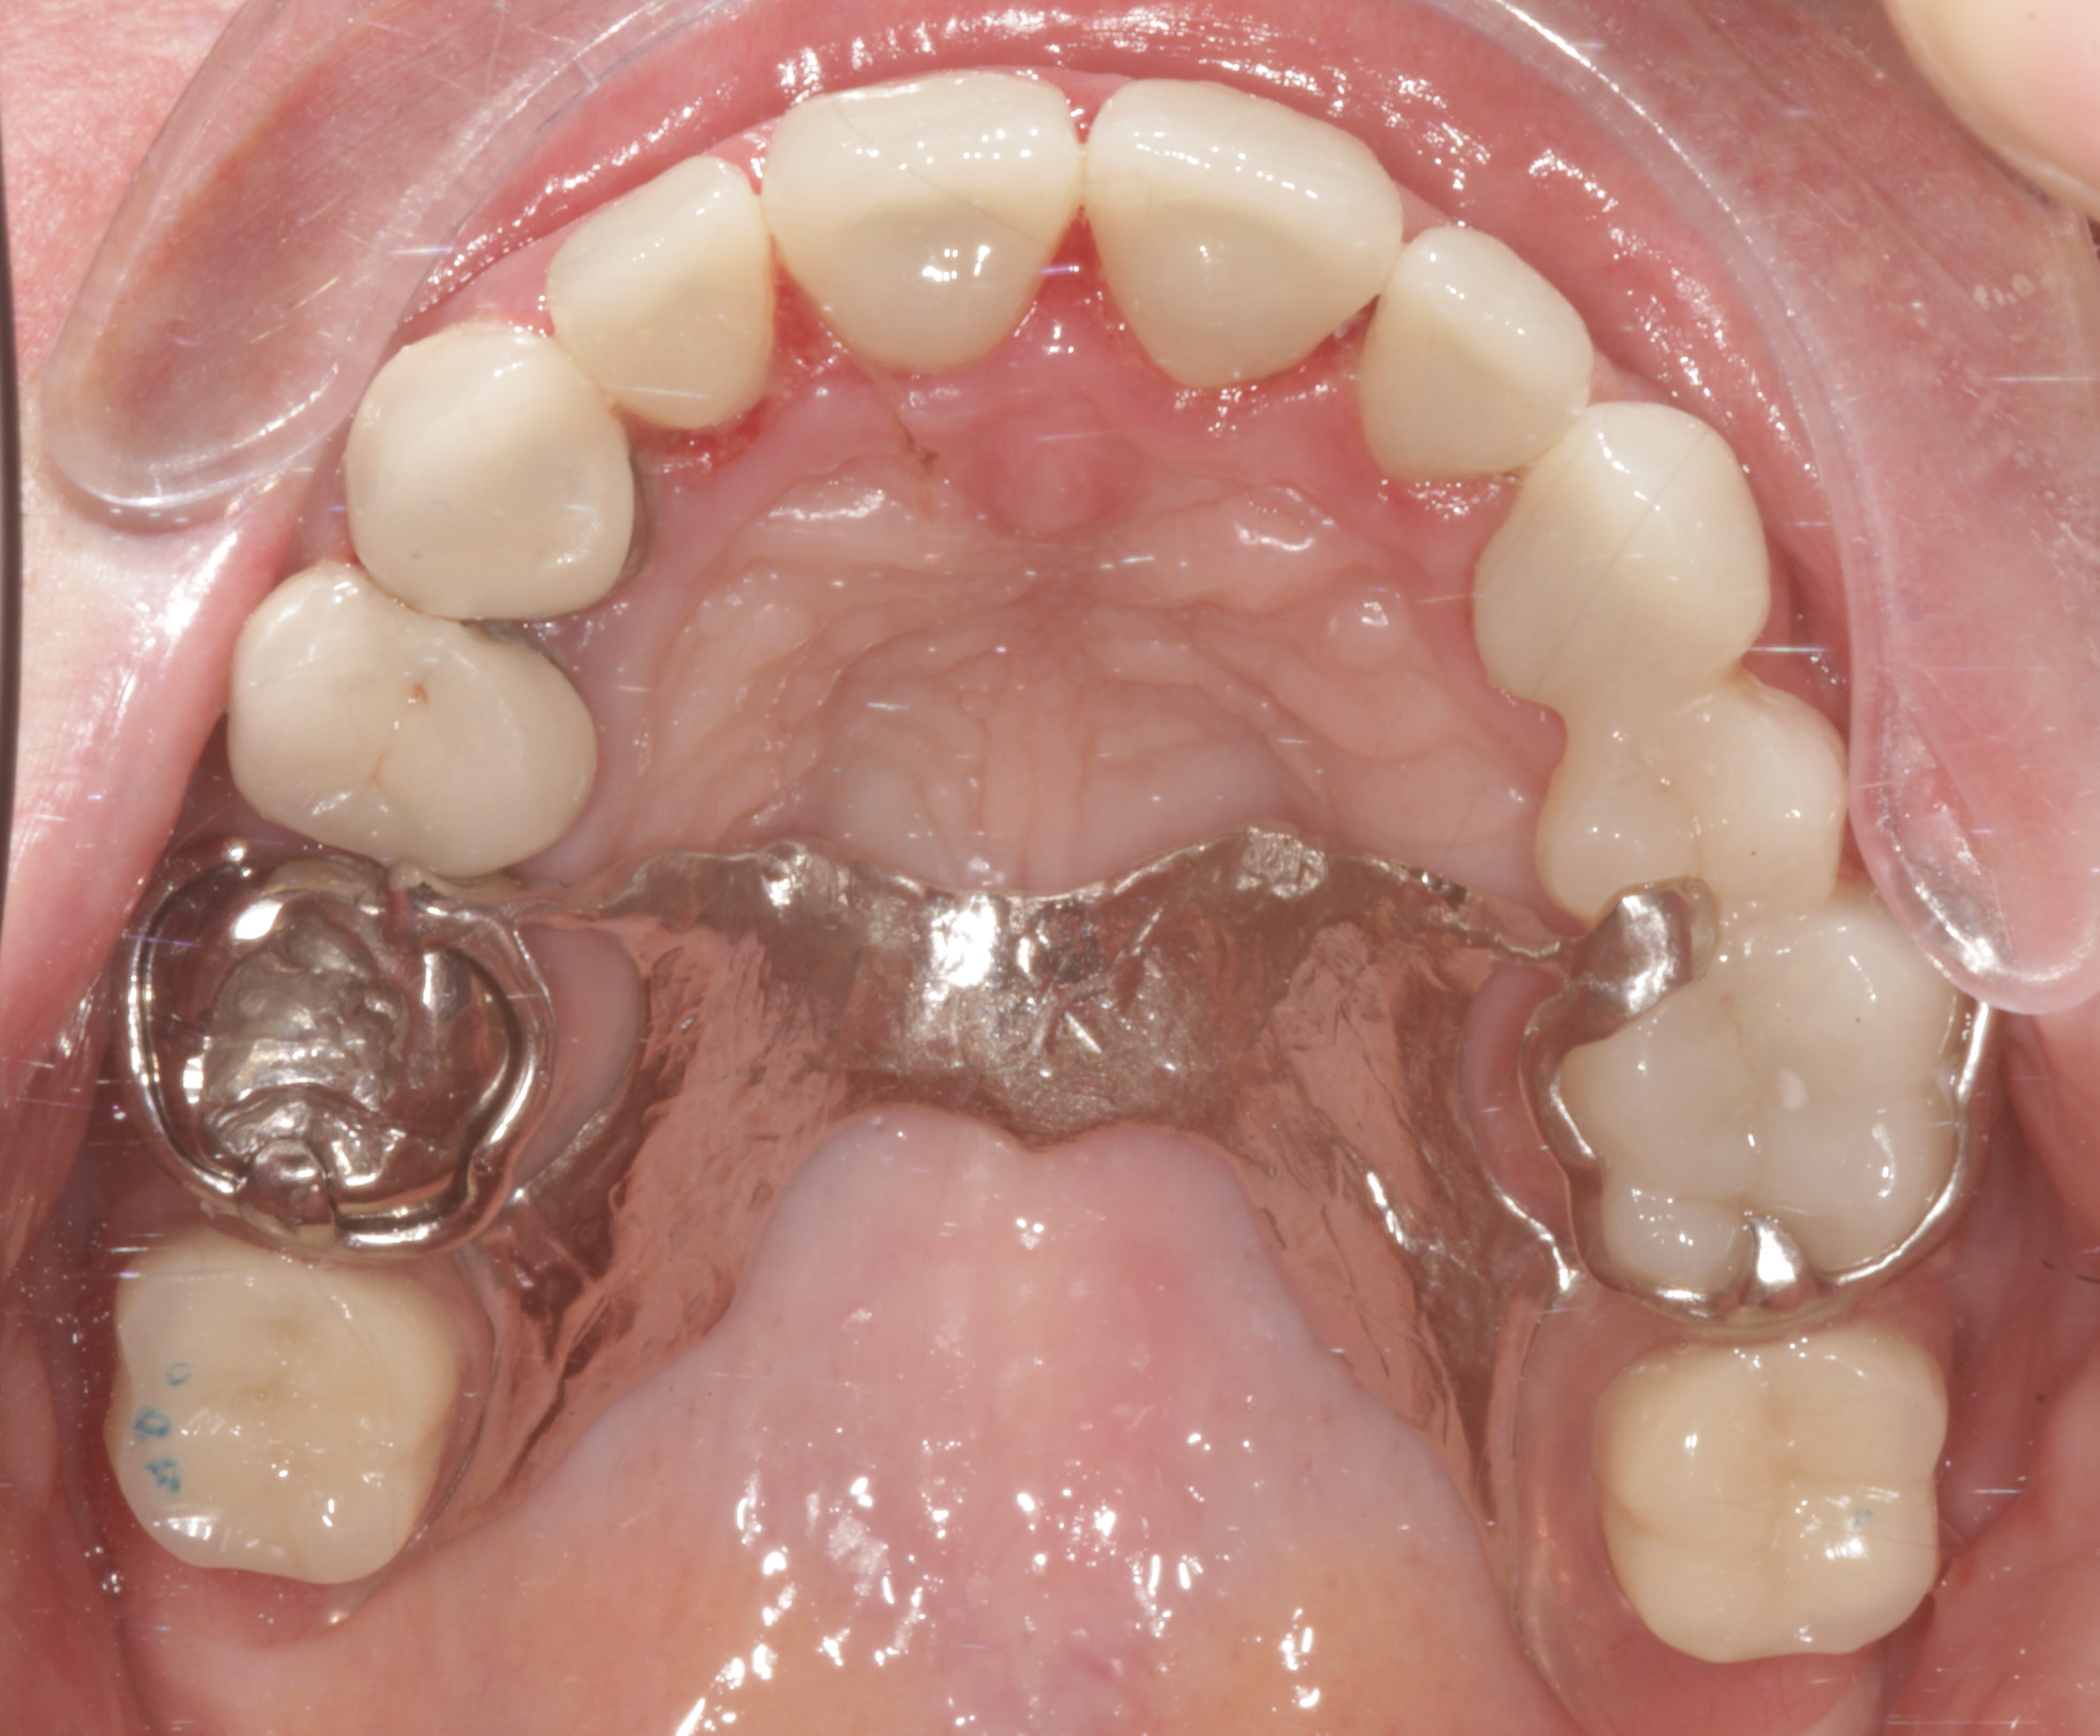

sur ce cas

Au max: 7 full , 5 ic et stellite

A la mand: 1 ic , 1 full ( support de crochet) et stellite

Le tout et je précise bien tout a été fait en flux numerique et ONE SHOT !

Les modèles sont imprimés a la fin ! Alors que ic,couronnes et stellites sont déja fabriqués.

Ce client nous précise qu’il n’a pas eu une seul retouches à faire

Ok ce sont des full , budget patient sans doute limité ..

Ok la camera utilisé n’est pas une i500

Mais quand même !